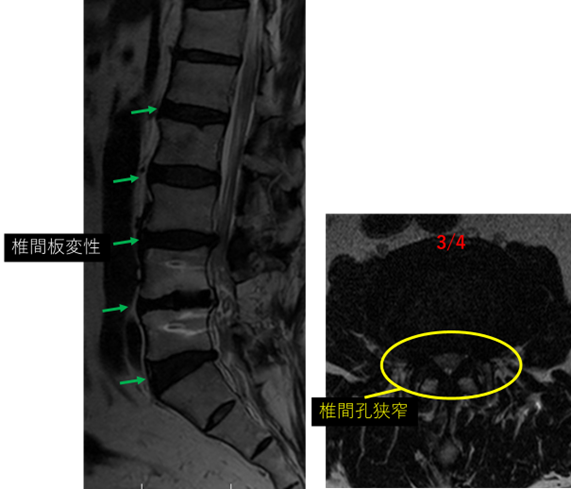

画像及び所見について

L1/2: なし

L2/3: 椎間板変性、椎間板膨隆

L3/4:椎間板変性、椎間板膨隆、軽度右椎間孔狭窄

L4/5: 固定術後

L5/S:椎間板変性、椎間板膨隆

以上の事が画像上認められます。

L2/3、3/4、5/S に

椎間板変性、椎間板膨隆、軽度右椎間孔狭窄 を認め、主症状の原因の可能性が高い。